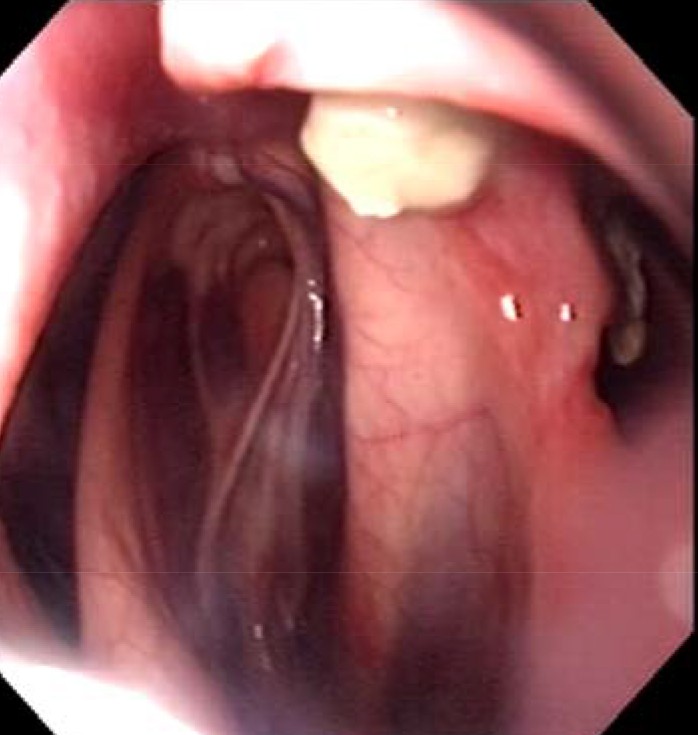

et les poches 5 semaines plus tard